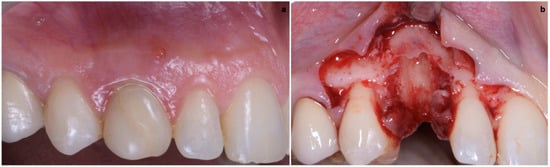

The buccal bone wall was extremely thin but partially maintained with 2 mm of buccal bone dehiscence (Figure 3a,b).

The surgical technique consisted in the execution of a lateral-approach coronally advanced envelope flap, which requires oblique submarginal interproximal incisions directed towards the flap’s center of rotation (in this case, the tooth to be extracted) (Figure 4a,b); the latter start from the gingival margin of the adjacent tooth and end at a distance from the vertex of the papilla that should equal the desired amount of coronal advancement of the marginal tissues. The flap was elevated in a split–full–split manner; a split-thickness incision was performed at the level of the surgical papillae by keeping the blade parallel to the bone; then, the central portion of the buccal flap was elevated in full thickness with a periosteal elevator until 2–3 mm of buccal bone was exposed. Apically, flap elevation continued, first with a “deep” split-thickness incision, keeping the blade parallel to the osseous plane and detaching the muscle insertions from the periosteum, and afterwards with a “superficial” one, placing the blade parallel to the external mucosal surface and controlling its movement using transparency while detaching the superficial muscle insertions from the inner aspect of the flap. This last incision is the one responsible for flap mobility [17]. Once the buccal flap was elevated, the atraumatic extraction of the canine was performed (Figure 5). Full visibility and access help to avoid both trauma to the anatomical papillae and damage to the buccal bone plate; special attention should be placed towards preserving the integrity of the anatomical papillae mesial and distal with respect to the canine, since they are essential for the surgery’s successful outcome.

Figure 4. (a,b) Lateral-approach coronally advanced envelope flap, with oblique submarginal interproximal incisions directed towards the flap’s center of rotation (the tooth to be extracted).